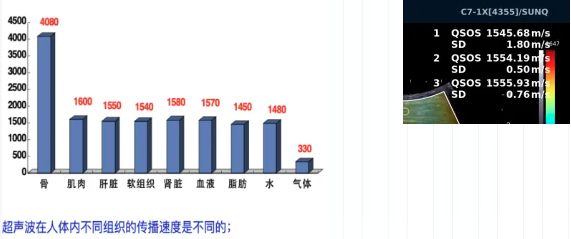

5G定量超声 | 声速定量成像QSOS,开启医疗诊断新思路

在医学诊断和研究中,超声成像技术一直是一个重要的工具。近来,3377体育医疗新推出的声速定量成像(Quantitative Speed of Sound Imaging,简称QSOS?)作为一种新兴的超声成像技术,正逐渐受到关注。这种新近问世的的超声成像技术,是通过测量超声波在不同组织中的传播速度,来反映不同器官或者病变的病理......